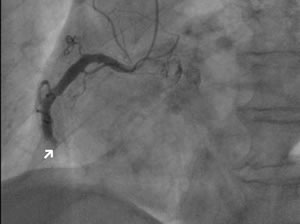

| PCI治療前と治療後 ■治療前 冠動脈造影検査で冠動脈がつまっている部分が確認できる |

![]() |

| ■治療後 PCI後。冠動脈の血流が回復している |